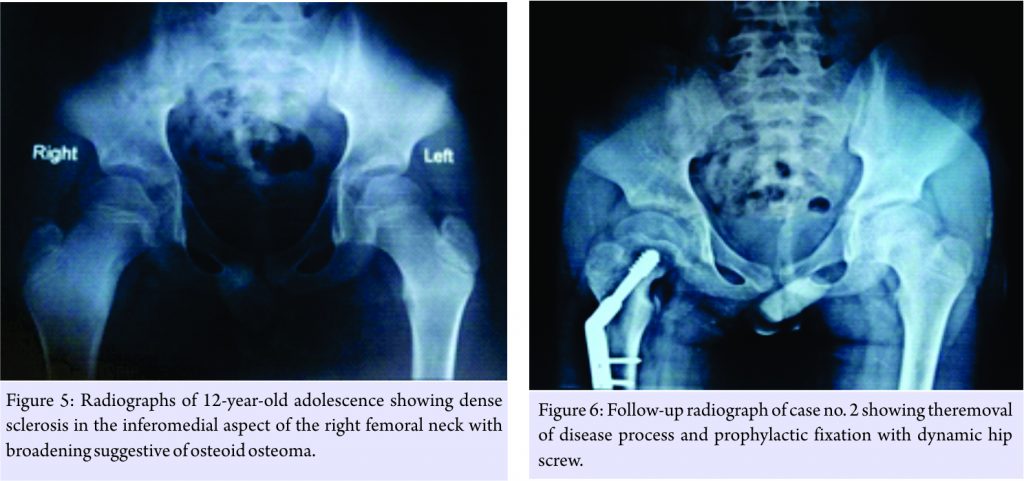

A 12-year-old adolescent male presented with 10 months history of pain in the right hip radiating down to anterior thigh. Initially, pain was intermittent in nature which gradually progressed over a period of time, limiting daily activities. Patient has been treated conservatively with oral antibiotics and anti-inflammatory drugs for past 2 months. He now often wakes up at night due to pain in the right groin. Parents noticed occasional limp for past 1.5 months. Movements in hip were terminally restricted with lengthening of affected limb by 1 cm. Radiographs showed dense sclerosis in the inferomedial aspect of the right femoral neck with broadening (Fig. 5). CT scan revealed eccentric lytic lesion with reactive bone sclerosis. Based on imaging studies, working diagnosis of osteoid osteoma was established. Lesion was approached anteriorly and excised completely; autologous bone grafting and prophylactic fixation with pediatric dynamic hip screw were done (Fig. 6). The histological examination confirmed the diagnosis of osteoid osteoma. Postoperatively, limb was protected for 3 weeks with gradual weight-bearing as tolerated. Patient’s hip pain completely resolved and remained symptoms free at 6 months of follow-up. He regained full range of motion in hip and normal functional status.